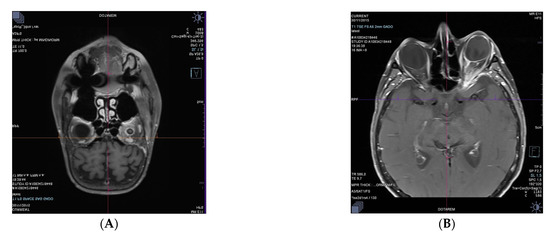

3.1.3. Case 3. Orbital Relapses in the Case of Systemic DLBCL, despite Auto and Allograft Transplant of Hematopoietic Stem Cells

3.1.4. Case 4. First Vitreous Relapse in the Case of Systemic DLBCL, despite CAR T-cell Therapy with Axicabtagene Ciloleucel. Second Retinal Relapse in the Form of a Retinitis after Pembrolizumab Infusions, Intravitreal Methotrexate, and Intrathecal Methotrexate